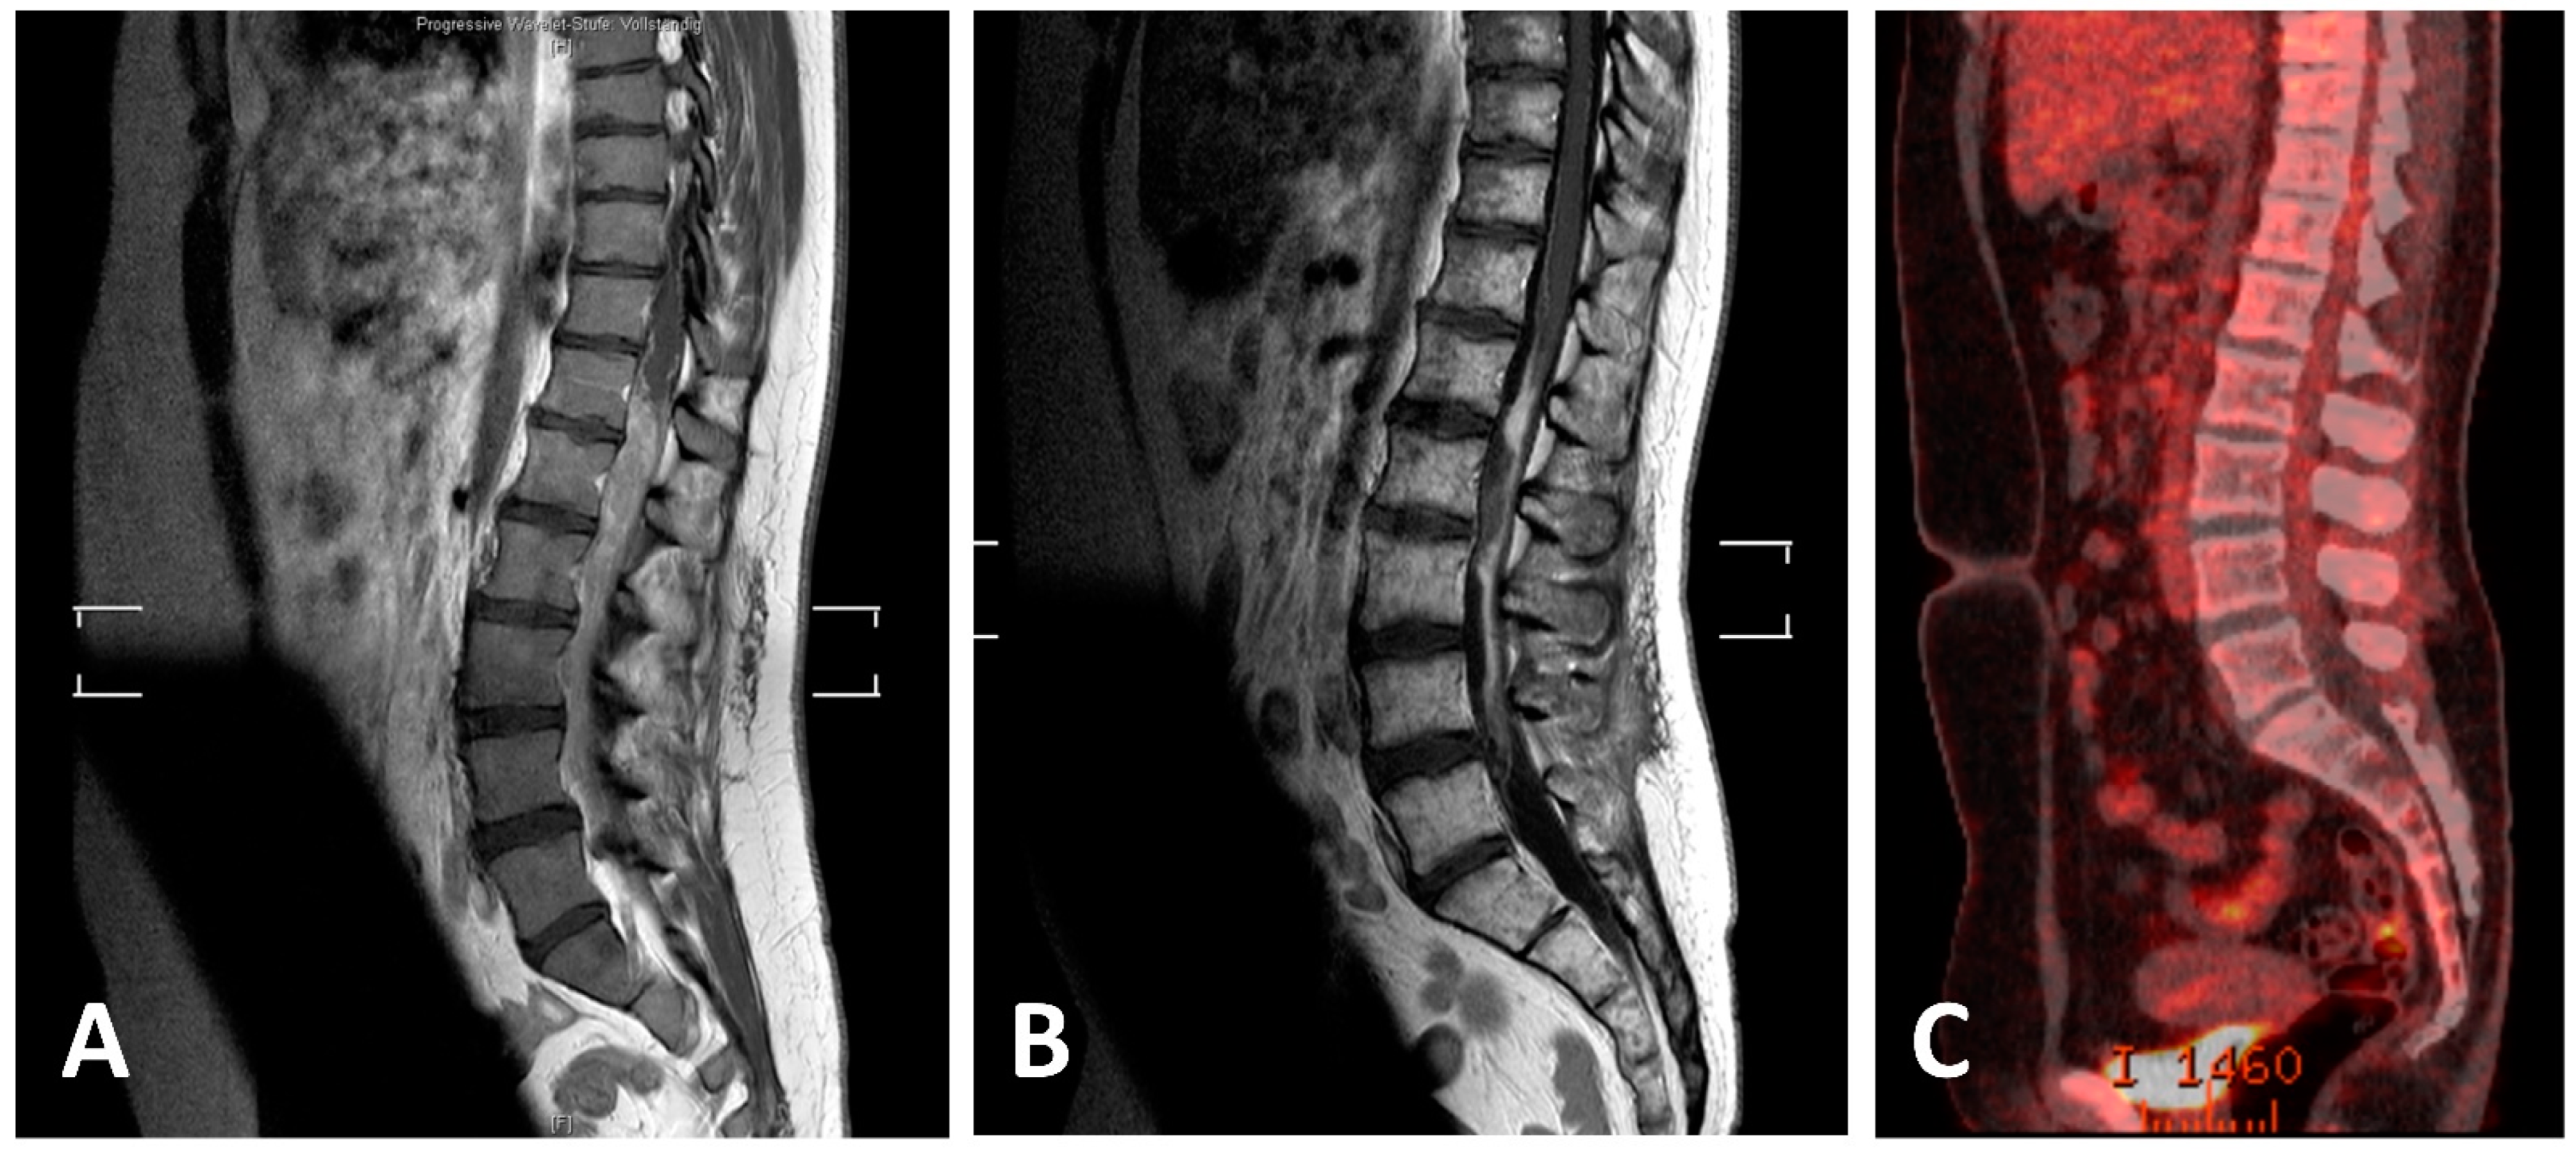

3.7. Own Case

One patient from our department with primary intradural extramedullary EwS disease received definitive combined radiochemotherapy (RCth) according to the European Ewing tumor Working Initiative of National Groups—Ewing Tumor Studies 1999 (EURO-E.W.I.N.G. 99) therapy protocol. The patient presented with lumbar pain, hypesthesia, and a beginning paresis of the left leg. Staging showed an intradural mass ranging from T12 to L5 (Figure 4) and malignant cells in the cerebrospinal fluid. After biopsy allowed for histopathologic diagnosis Cth with six cycles of systemic VIIE (vincristine, idarubicin, ifosfamide, etoposide) and one cycle of intrathecal methotrexate was applied. Then, definitive RT including CSI with 36 Gy in 1.5 Gy fractions and a boost to the tumor region from level T12 to L5 up to a dose of 54 Gy was performed. Consolidating chemotherapy with 4 cycles of VEI (vincristine, etoposide, and ifosfamide) and a high-dose chemotherapy (HD-Cth) was then followed by autologous stem cell transplantation. Afterwards, two additional cycles of VEI were given and FDG-PET/CT, MRI, and cerebrospinal fluid showed a complete response (Figure 4). Thirty-eight months after the end of the therapy, the latest follow-up showed no sign of new disease.

Figure 4. MRI and PET-CT scans of lumbar EwS before and after definitive RCth (radiochemotherapy) and ASCT (autologous stem cell transplantation). (A) Initial T1-weighted sagittal MRI of the thoracic and lumbar spine with intramedullary tumor; (B) T1-weighted sagittal MRI with residual post-therapeutic signal alterations; (C) post-therapeutic PET-CT scan with no residual increased FDG uptake.